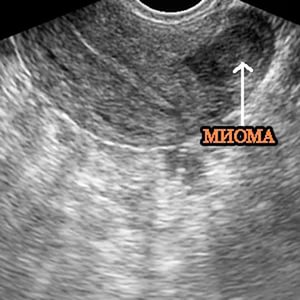

Шеечная миома матки диагностируется гораздо проще, чем остальные типы таких новообразований. Хотя она, как и большинство других типов миом, протекает бессимптомно. Однако за счет ее относительно не скрытого расположения, она порой может быть диагностирована случайно. Например, в ходе планового гинекологического осмотра, даже без УЗИ. В общем случае для постановки диагноза используются следующие методы:

- УЗИ – наиболее информативный метод из доступных, и часто назначаемый;